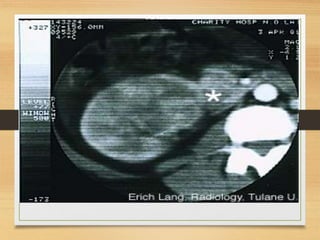

Radiological

• U/S

• C.T

CASE 4

• A 64-year-old man presents with a 2-month history

of painless visible haematuria, hypertension, weight

loss, loin swelling and anaemia. What is the most

likely diagnosis?